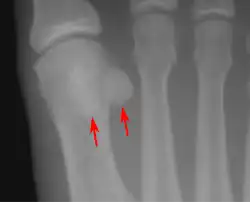

Sesamoid bones at the distal end of the first metatarsal bone of the foot.